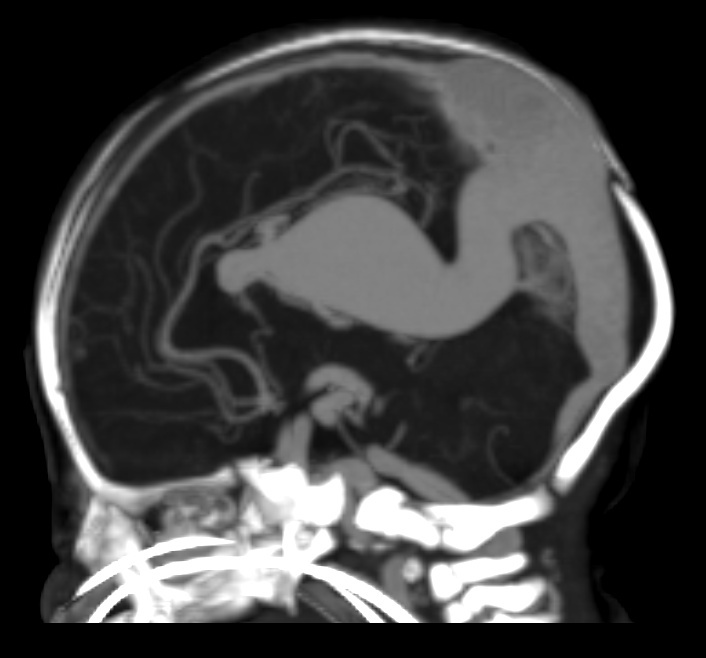

CT and MRI

Both CT and MRI can be used to delineate the malformation cross-sectionally.

CT angiography

CTA in neonates with high output cardiac failure is technically-challenging due to the small volumes of contrast and very rapid passage of contrast through the circulation.

MR angiography

The dilated feeding and draining vessels appear as flow-voids on T2. MRA may also be performed which would better delineate vascular anatomy.

Angiography

Angiography remains the gold standard in full characterisation of the lesion. It enables to individually catheterise feeding vessels. Morphologically a spherical or ellipsoid varix may be visualised. Venous drainage is via the median prosencephalic vein (MPV), the straight sinus (if present) and then out via the transverse/sigmoid sinuses. By definition, there should be no drainage to other components of the deep venous system 6.